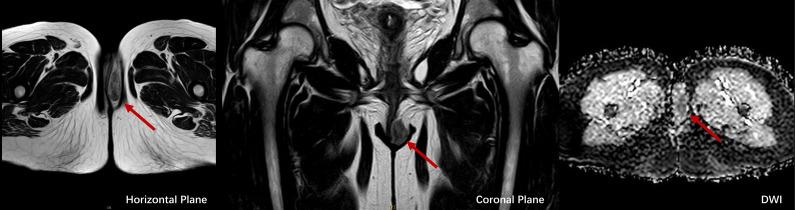

Low-grade myofibroblastic sarcoma (LGMFS) of the vulva is exceptionally rare, with only two prior cases reported. We present the third documented case globally and the first occurring during pregnancy, highlighting diagnostic and therapeutic challenges in this unique clinical scenario. A 34-year-old woman presented with a recurrent vulvar mass initially misdiagnosed as angiomyofibroblastoma. The lesion reappeared asymptomatically during pregnancy and was conservatively managed with ultrasound surveillance, followed by term cesarean delivery to mitigate perineal trauma risks. Postpartum evaluation revealed a 3.7 cm T2-hyperintense nodule on MRI. Although intraoperative frozen sections suggested benign margins, definitive histopathology and molecular studies (CD34+/SMA+; FISH-negative for COL1A1::PDGFB fusion and MDM2 amplification) confirmed LGMFS. Radical vulvectomy with 2 cm margins achieved disease-free survival at 17 months without adjuvant therapies. This case underscores that LGMFS may recur silently during pregnancy, necessitating rigorous histopathological re-evaluation of prior benign diagnoses. Multidisciplinary coordination enabled safe deferral of definitive surgery until postpartum without compromising outcomes, while radical excision alone proved curative, reflecting the tumor's indolent biology. Our findings establish the first pragmatic framework for managing vulvar LGMFS in pregnancy, emphasizing tailored surgical planning over routine adjuvant interventions.

外阴低度恶性肌成纤维细胞肉瘤(LGMFS)极为罕见,此前仅报道过两例。我们报告了全球第三例有记录的病例,也是首例发生在孕期的病例,突出了这种独特临床情况下的诊断和治疗挑战。一名34岁女性出现复发性外阴肿物,最初被误诊为血管肌成纤维细胞瘤。该病变在孕期无症状复发,通过超声监测进行保守处理,随后足月剖宫产以降低会阴创伤风险。产后评估显示磁共振成像(MRI)上有一个3.7厘米的T2高信号结节。尽管术中冰冻切片提示切缘良性,但最终的组织病理学和分子研究(CD34+/平滑肌肌动蛋白+;FISH检测COL1A1::PDGFB融合和MDM2扩增均为阴性)确诊为LGMFS。切缘2厘米的根治性外阴切除术实现了17个月无病生存,未进行辅助治疗。该病例强调LGMFS可能在孕期悄然复发,需要对先前的良性诊断进行严格的组织病理学重新评估。多学科协作使得能够安全地将确定性手术推迟到产后而不影响治疗效果,同时仅根治性切除就证明具有治愈性,反映了肿瘤的惰性生物学行为。我们的研究结果建立了首个针对孕期外阴LGMFS管理的实用框架,强调定制化手术规划而非常规辅助干预。